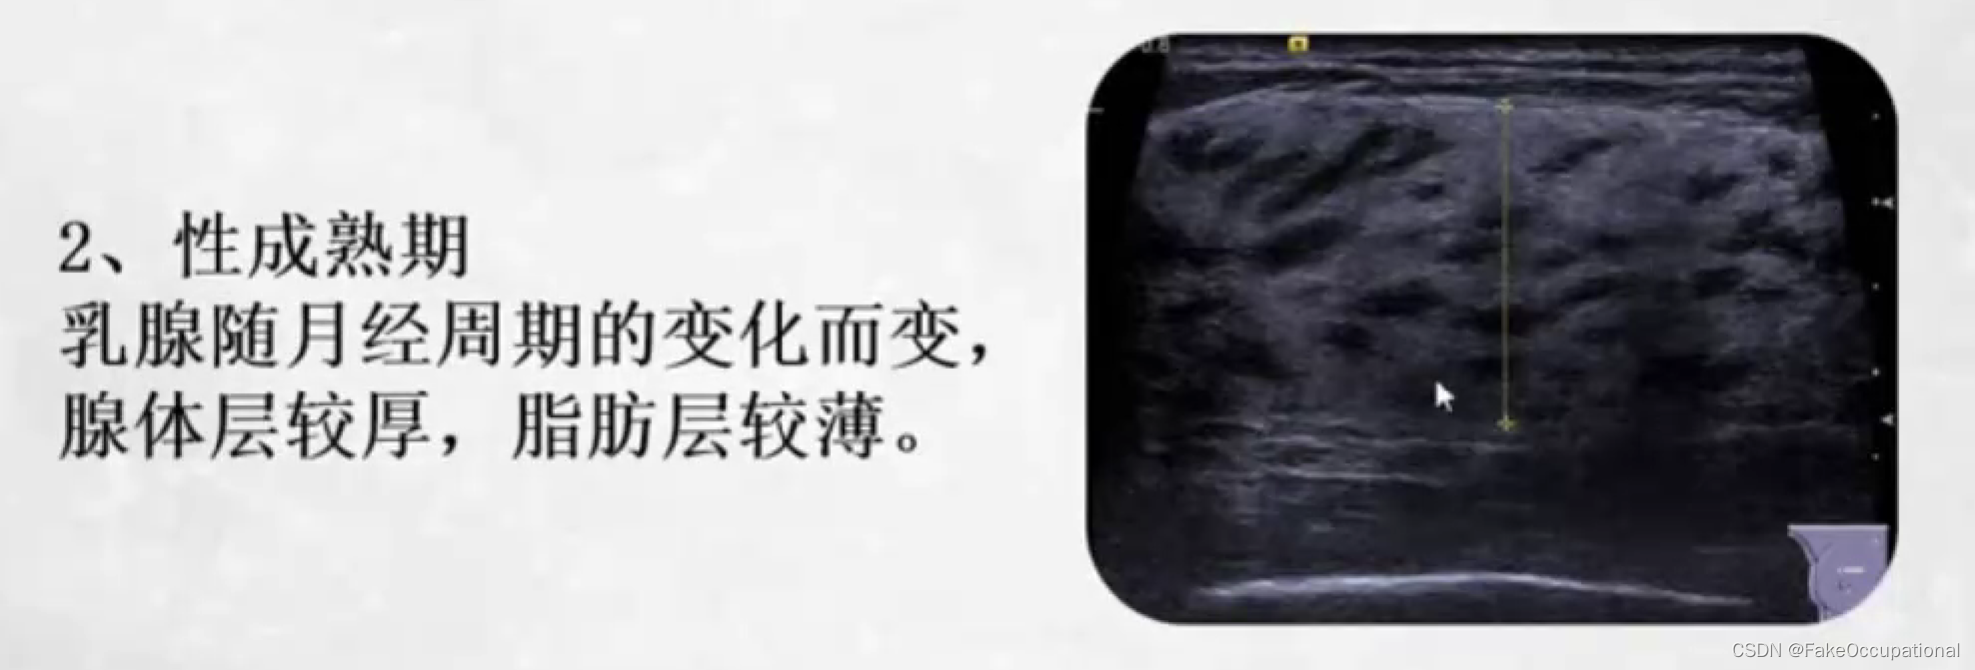

乳腺的生理解剖概要

乳腺的生理解剖概要